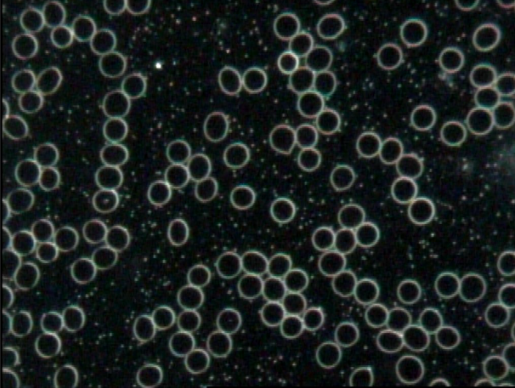

Blood sample using Dark Field Microscopy showing Red Blood Cells

Cellular Health Assessment: Live blood analysis provides a dynamic assessment of the health and vitality of individual blood cells. By observing the blood live, practitioners can evaluate the shape, size, movement, and behaviour of red blood cells, white blood cells, platelets, and other cellular components. This level of detail can offer valuable insights into cell membrane integrity, oxidative stress, nutritional deficiencies, and overall cellular health.